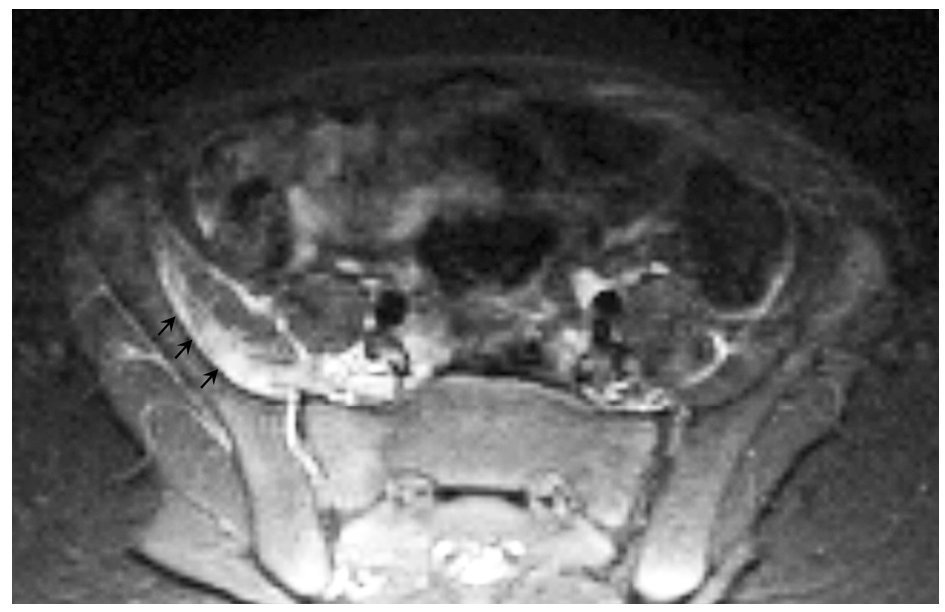

La tabla 3 muestra los hallazgos radiológicos. La radiología simple realizada a todos los pacientes resultó inespecífica; de los 8 casos a los que se realizó ecografía articular sólo dos fueron positivas, encontrando hallazgos inespecíficos (aumento de tejido celular subcutáneo y derrame articular). La gammagrafía ósea vascular realizada a 9 pacientes mostró focos de captación en 4 de ellos. La RM identificó la musculatura afectada, la presencia de abscesos y la afectación ósea subyacente. Las secuencias STIR en RM mostraron la musculatura afectada como zonas de hiperseñal (fig. 1). En secuencias espín eco la musculatura afectada presentaba un aumento de tamaño, con una disminución difusa de la señal en secuencias potenciadas en T1 y un aumento de señal en secuencias T2. En estadios precoces no existían colecciones focales de líquido, y tras la administración de contraste endovenoso existía realce heterogéneo.

Fig. 1. Secuencia STIR que muestra la hiperseñal del músculo psoas ilíaco y mínimo derrame articular en la articulación sacro-ilíaca derecha.